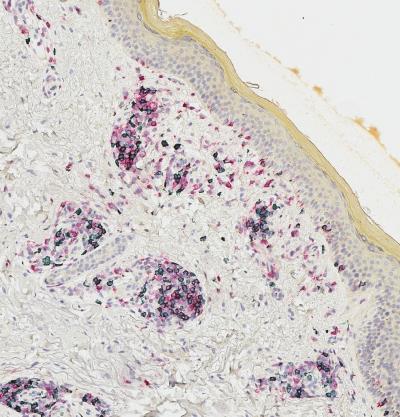

LEBANON, NH - Some melanoma patients respond very well to immunotherapy, experiencing profound and durable tumor regression. A fraction of these patients will also develop autoimmunity against their normal melanocytes--the cells that give rise to melanoma--a phenomenon called vitiligo. Melanoma survivors with vitiligo have long been recognized as a special group with an outstanding prognosis, and a strong response of immune system cells called T cells.

Turk's and Angeles' study found that T cells that enter melanoma tumors also have a tendency to enter a patient's vitiligo-affected skin; that skin accumulates a more focused repertoire of tumor-related T cells than does blood; and that T cells in melanoma tumors are genetically and molecularly very similar to those in vitiligo-affected skin. With these findings, the research team then identified a new subset of "resident memory" (TRM) cells that localize to patient skin and tumor and make high levels of the cytokine interferon gamma. TRM-IFNγ cells have a unique gene expression profile, or "signature," found in melanoma tumors from patients who have survived longer than those who don't have the signature. Turk and Angeles found that T cells that infiltrate tumors have matching clonal partners, or daughter cells, that persist in patient skin and blood up to nine years later.

The team's findings, entitled " Resident and circulating memory T cells persist for years in melanoma patients with durable responses to immunotherapy ," are newly published in Nature Cancer . No prior study has demonstrated cellular evidence of such long-lived immunity to cancer. The extensive collaboration between scientists, surgeons, and oncologists required harvesting tumors, blood, and skin from melanoma patients over a period of several years. Patient specimens were analyzed using state-of-the-art technologies called single cell RNA sequencing and T cell receptor sequencing.